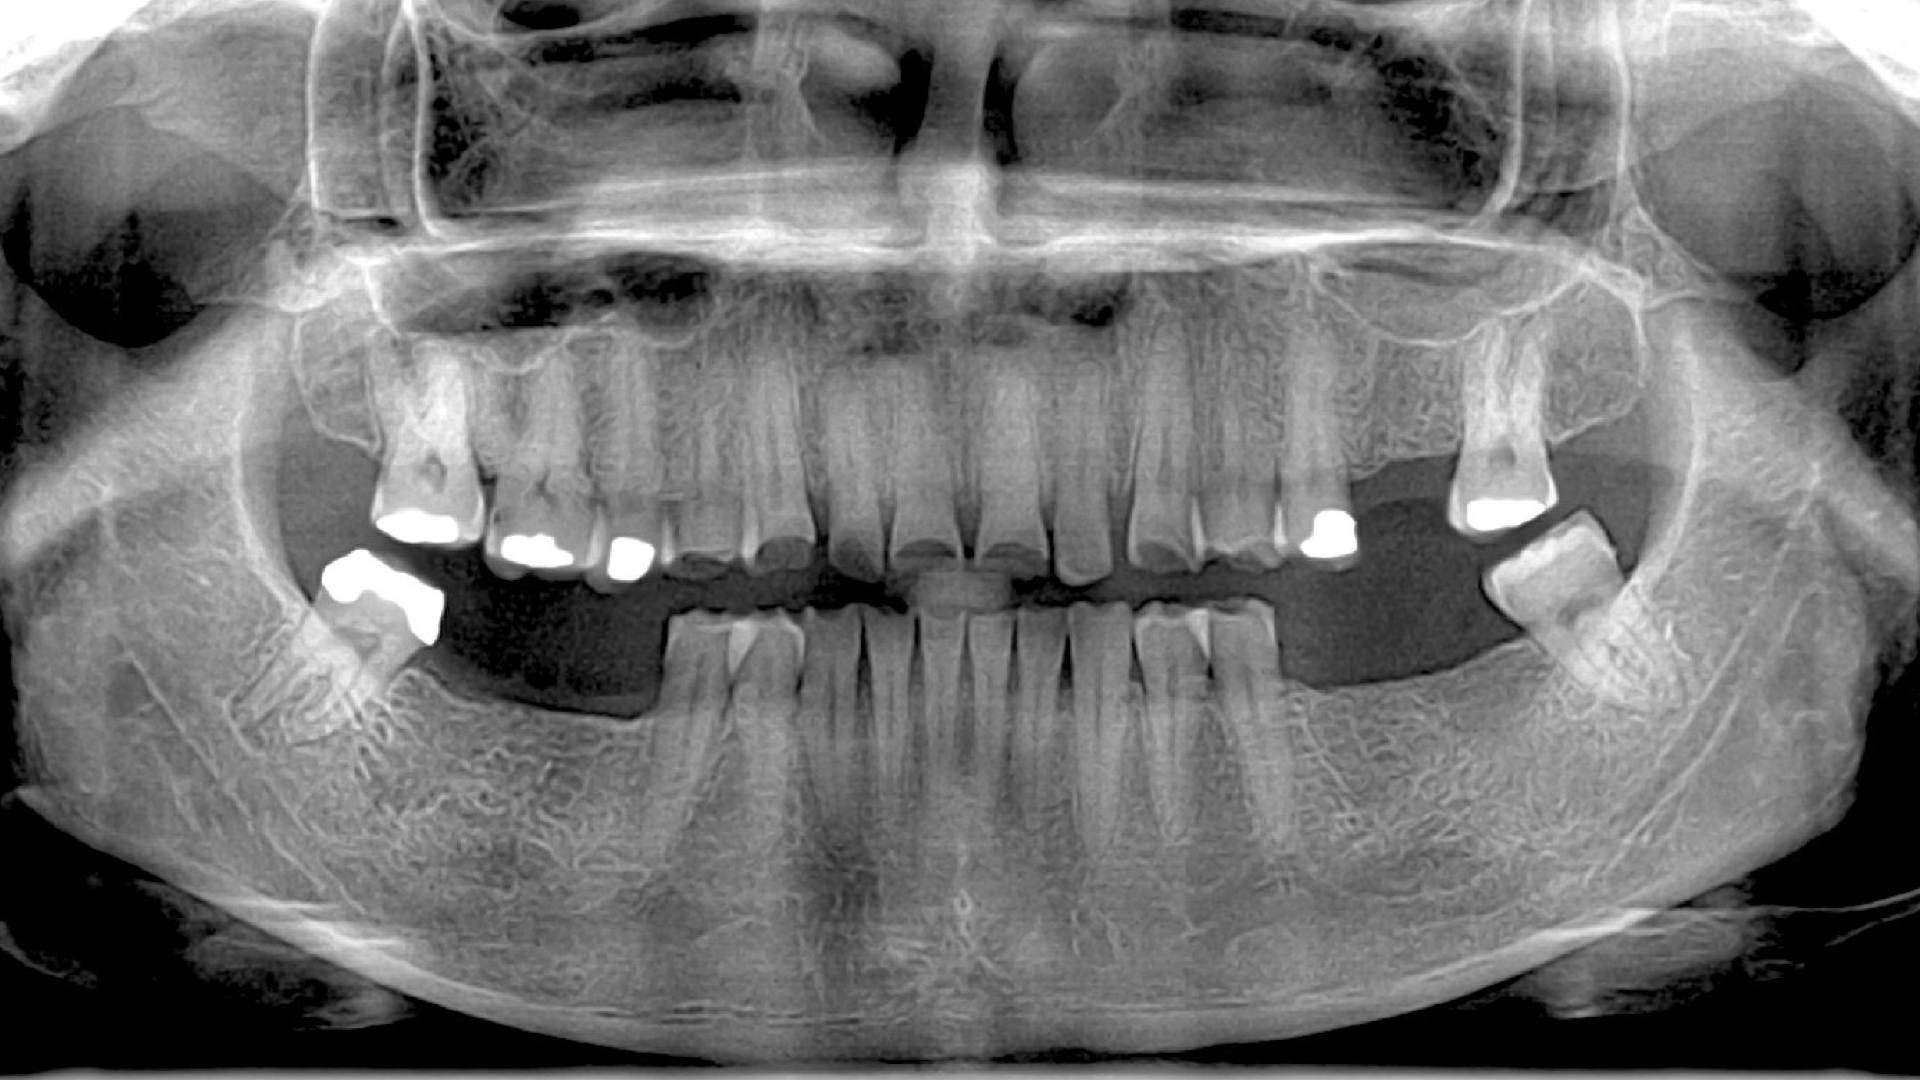

La paciente acudió debido al desgaste dental severo que presentaba, este problema le estaba ocasionando dificultades masticatorias, problemas digestivos y alteraciones en su estética

La paciente acudió debido al desgaste dental severo que presentaba, este problema le estaba ocasionando dificultades masticatorias, problemas digestivos y alteraciones en su estética, lo que la llevaba a sentir que ya no quería reír ni socializar.

Le propuse obtener toda la información posible y realizar un Diseño de Sonrisa para analizar su caso. Este caso se llevó a cabo en 2014 y se realizó de manera analógica, siguiendo métodos clásicos de esa época.